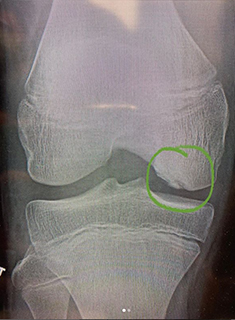

Surgical management is indicated when nonsurgical management fails, in unstable lesions, or when loose bodies are present. When surgery is done for these lesions the goal is maintain articular cartilage congruity, repair the defect, and fix unstable fragments. Figure 1 shows a young soccer athlete with an OCD lesion and Figure 2 shows the lesion healed 6 months after in situ fixation.

Figure 1